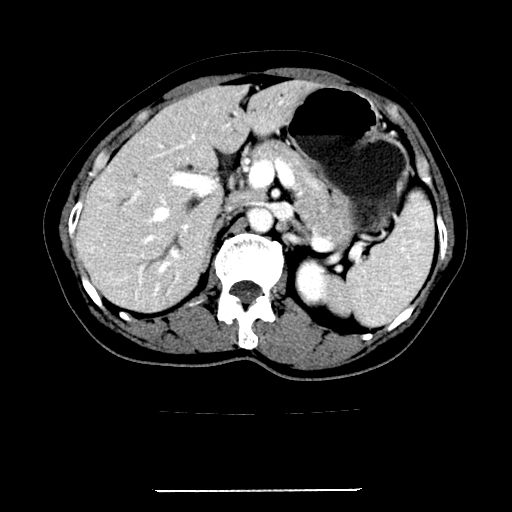

标题: CT22301:女,67岁,上腹部疼痛一周伴皮肤黄染,无发热。 [打印本页]

女,67岁,上腹部疼痛一周伴皮肤黄染,无发热。

左叶肝内胆管结石,并远端肝内胆管扩张。

考虑:肝内胆管结石继发肝内胆管扩张,右肾旋转不良。

肝内外胆管结石并肝内胆管扩张。

肝内外胆管结石并肝内胆管扩张

肝内外胆管扩张,左叶胆管内结石

建议薄层观察,除外肝门部胆管细胞癌

考虑肝胆管癌;胰头占位?【形态失常,体积增大】

1、肝门高密度影下层面和胰头层面可见轻度胆管扩张,而静脉和延迟期均未见扫描完胰头,不能完全排除胰头占位。2、肝门部高密度影,考虑钙化或结石。

考虑肝门胆管癌伴门脉左支受侵包埋,建议mrcp进一步检查。

肝内胆管结石并胆管扩张